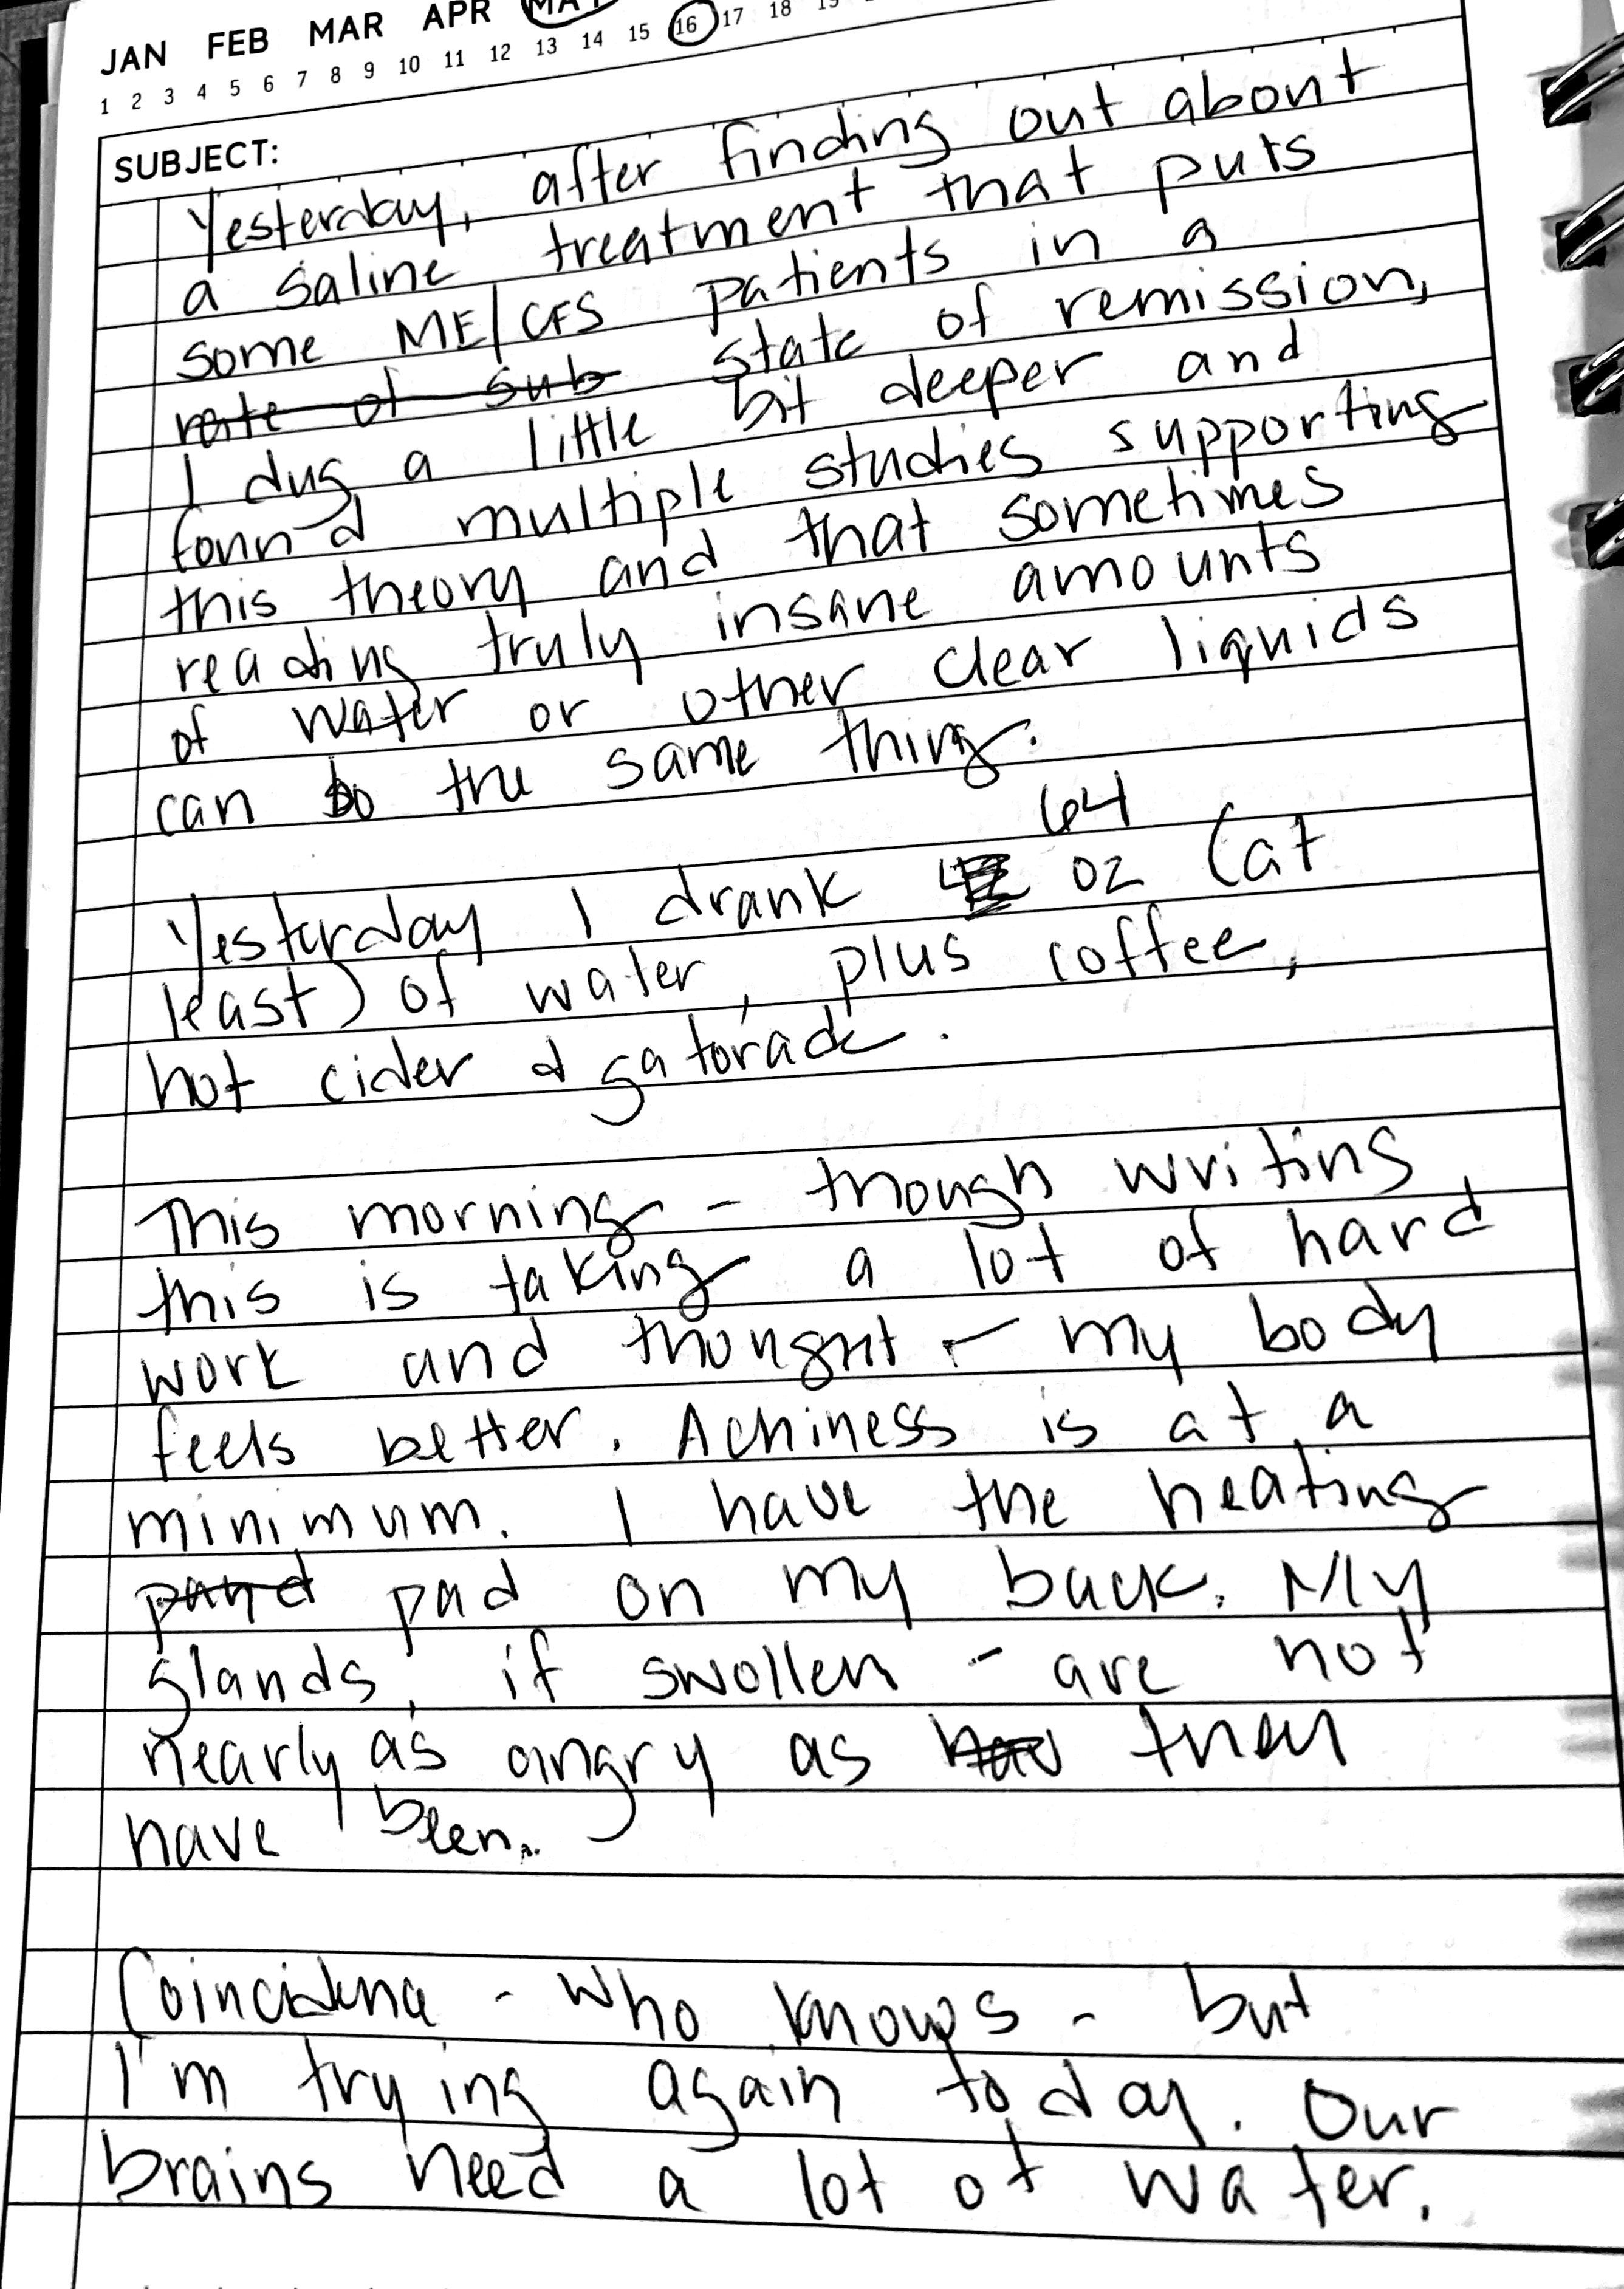

Given where I am today: much improved, but still battling cognitive issues, fatigue, weakness, and radiating pain, S. (my son), decided it was time to do as full a medical history on me as he could. I gave him full access to my medical records and answered questions as they came up. My husband and I used to IM each other when we had office jobs so I was able to do some digging in that history to help S’s timeline and his pharmaceutical history.

Every health issue I can remember got its own page on a legal pad with details. As I mentioned, there was as full a pharmaceutical workup as he could do without my psych records. To call this study thorough, thoughtful, and accurate would be a compliment for a true M.D., but to see it created by S. was – I don’t want to say “surprising” because he’s shown this gift for a long time. Maybe the better words is “impressive.” After a whole lot of work, he found the source of my ME/CFS. My hypothalamus is overactive.

Basically, my unresolved PTSD has caused my hypothalamus to continually flood my nervous system with cortisol and norepinephrine. This is why NSRI’S work for me while SSRI’s don’t. The pressure on the nerves in my spine prior to surgery likely aggravated this further.

If you read medical journals deeply, you’ll see where scientists are finding this link and doing further testing.